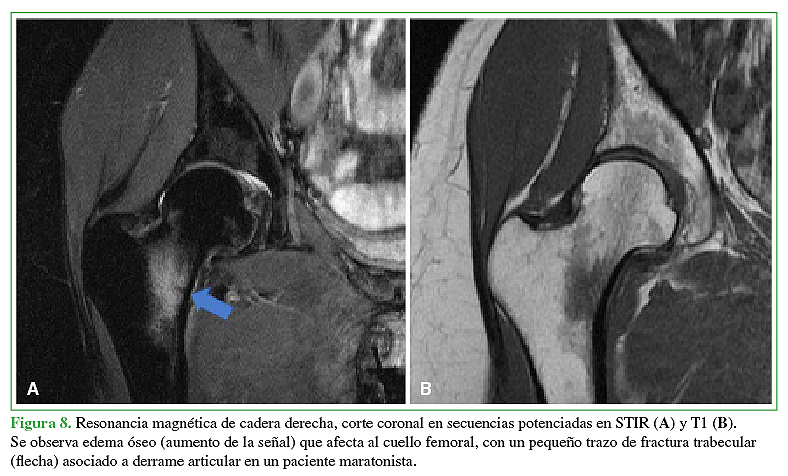

Acceso mediante suscripción PDF Acceso mediante suscripción PDF_EN (English) Acceso mediante suscripción Figura 1 Acceso mediante suscripción Figura 2 Acceso mediante suscripción Figura 3 Acceso mediante suscripción Figura 4 Acceso mediante suscripción Figura 5 Acceso mediante suscripción Figura 6 Acceso mediante suscripción HTML